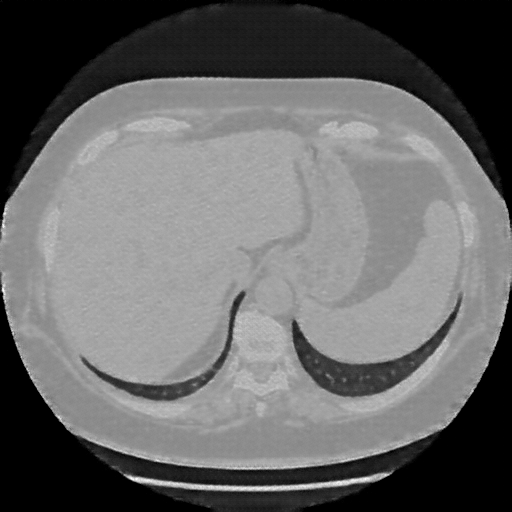

Generated VENOUS CT scan (A→B translation)

Full window (WL 1023.5, WW 4095 β†’ Low βˆ’1024, High +3071)